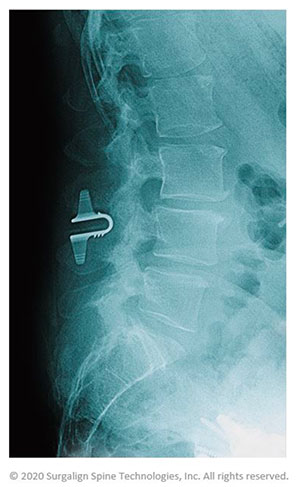

How the new Coflex implant improves outcomes from stenosis surgery

The Coflex device is a motion-preserving titanium implant implanted in the low back after lumbar spinal stenosis surgery. After your surgeon performs a direct decompression that removes bone, facet, ligament and/or disc segments from the narrowing in the spinal canal, the spine can become unstable. The traditional way this instability is addressed is with a spinal fusion, where a bone graft is inserted and ultimately fused to the vertebrae above and below. However, locking the vertebrae can sometimes put additional pressure on the remaining disc levels, potentially causing other disc herniations.

The Coflex implant is designed to keep the spine stable while maintaining normal height and motion in your spine. This new implant reduces the stress on the other disc levels. The Coflex implant procedure includes the following steps.

- After a microsurgical direct decompression, the motion-preserving device is implanted through a minimal incision and is placed on the lamina (the strongest posterior bone in the spine) to keep your spine stable

- This placement off-loads facet joints, maintaining the height between your bones for nerves to exit freely

The design of the Coflex device when implanted after stenosis surgery off-loads weight from the facet joints that would otherwise cause leg and back pain symptoms. The Coflex device helps the vertebrae move in a controlled manner. Patients who suffer from both leg and/or back pain caused by lumbar spinal stenosis are candidates for interlaminar stabilization with the Coflex device.